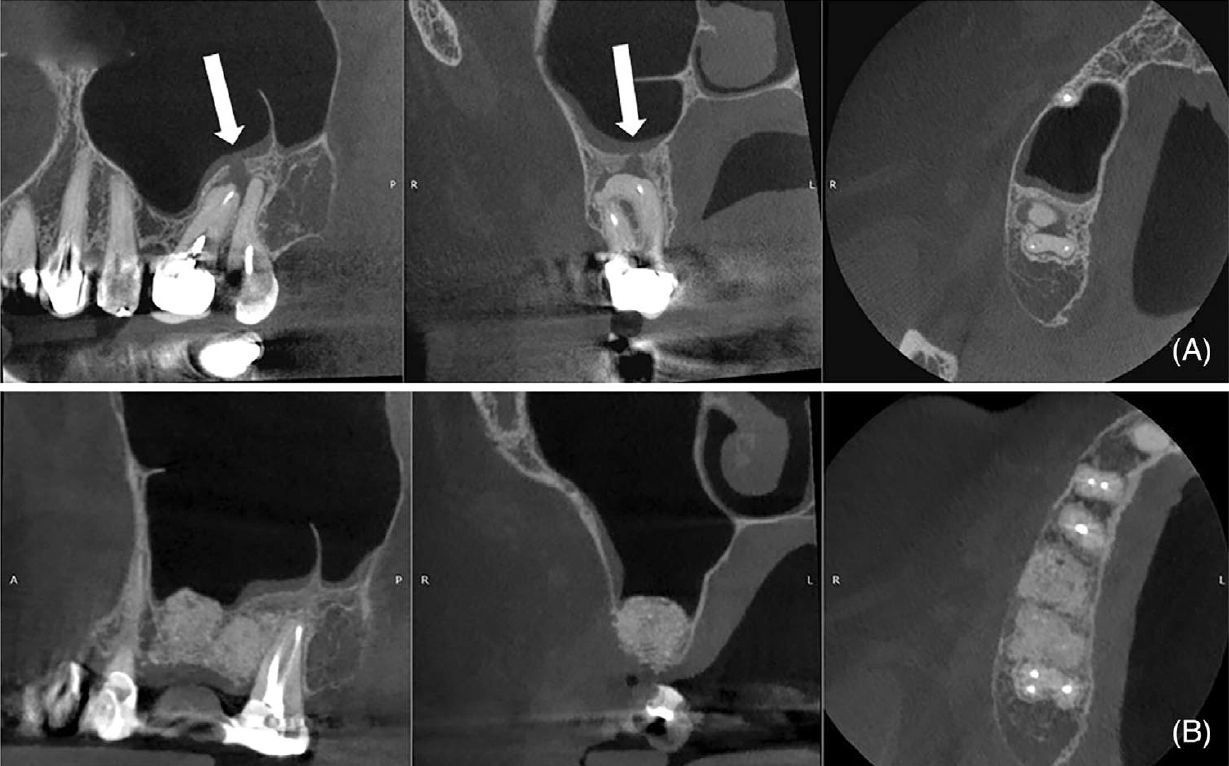

Фото 2. (A) Исходное КТ зуба 17 (сагиттальная, корональная и аксиальная проекции), демонстрирующее крупный участок сниженной плотности костной ткани, зубной камень (стрелка), кариес в области фуркации и сохранённую щёчную кортикальную пластинку. (B) КТ через 14 месяцев после операции (сагиттальная, корональная и аксиальная проекции), демонстрирующее образование кости на дистальной поверхности зуба 17 и ремоделирование апикальной и небной областей зуба 16. Линия, пониженной плотности, наблюдаемая в апикальной трети щёчных корней, соответствует репаративной ткани (коллагенизация)

Фото 5. (A) Исходное КТ (сагиттальная, корональная и аксиальная проекции), демонстрирующее очаг пониженной плотности вокруг зубов 16 и 15, фенестрацию щёчной кортикальной пластинки и утолщение слизистой оболочки верхнечелюстной пазухи. (B) КТ через 10 месяцев после операции (сагиттальная, корональная и аксиальная проекции), демонстрирующее образование кости, апикальное ремоделирование зуба 15, сохранение объёма тканей и нормализацию состояния слизистой оболочки верхнечелюстной пазухи

Фото 8. (A) Исходное КТ (сагиттальная, корональная и аксиальная проекции), демонстрирующее очаг пониженной плотности в области зубов 18 и 17, утолщение слизистой оболочки верхнечелюстной пазухи, кортикальную фенестрацию и ороантральное сообщение (стрелки). (B) КТ через 6 месяцев после операции (сагиттальная, корональная и аксиальная проекции), демонстрирующее образование кости, нормализацию состояния слизистой оболочки пазухи, восстановление кортикальной пластинки и закрытие ороантрального сообщения